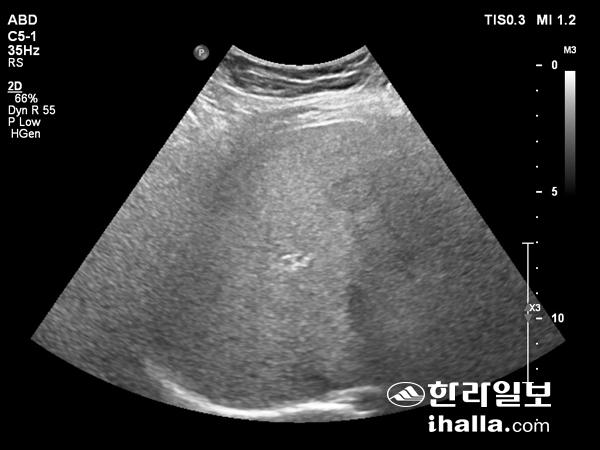

지방간질환은 증상이 없는 경우가 많다. 대부분 초음파 검사에서 우연히 발견되거나, 간효소 수치의 상승이 있어 초음파 검사를 실시한 후 진단된다. 일부 환자에서는 우상복부가 불편하게 느껴지거나 피로감 등의 증상을 보이는 경우도 있다.

지방간의 초음파사진

진단은 병력 청취 및 혈액검사를 통해 B형 및 C형 간염, 알코올 간질환, 약물 유발 간질환, 자가면역 간질환 등을 배제하고, 복부 초음파검사 등을 통해 간 내 지방침착을 확인해 진단하게 된다. 최근에는 초음파 원리를 이용한 간섬유화스캔검사가 지방침착 정도와 간섬유화 혹은 간경변으로의 진행을 함께 평가할 수 있어 많이 사용되고 있다. 간 조직검사는 진단의 기준검사이지만 고비용, 합병증 발생의 위험 때문에 꼭 필요한 환자에게 제한적으로 이뤄진다.